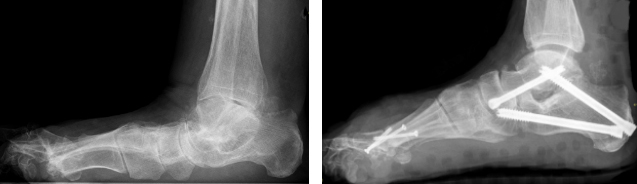

Auch Versteifungen des unteren Sprunggelenkes können, wenn keine gravierenden Fehlstellungen bestehen, mittels arthroskopischer Technik vorgenommen werden. Sind starke Fehlstellungen vorhanden, wird die Versteifung gleichzeitig mit der Achskorrektur über einen offenen Hautschnitt vorgenommen.

Versteifung des unteren Sprunggelenkes mit gleichzeitiger Versteifung des Chopartgelenks und Prothese des oberen Sprunggelenkes